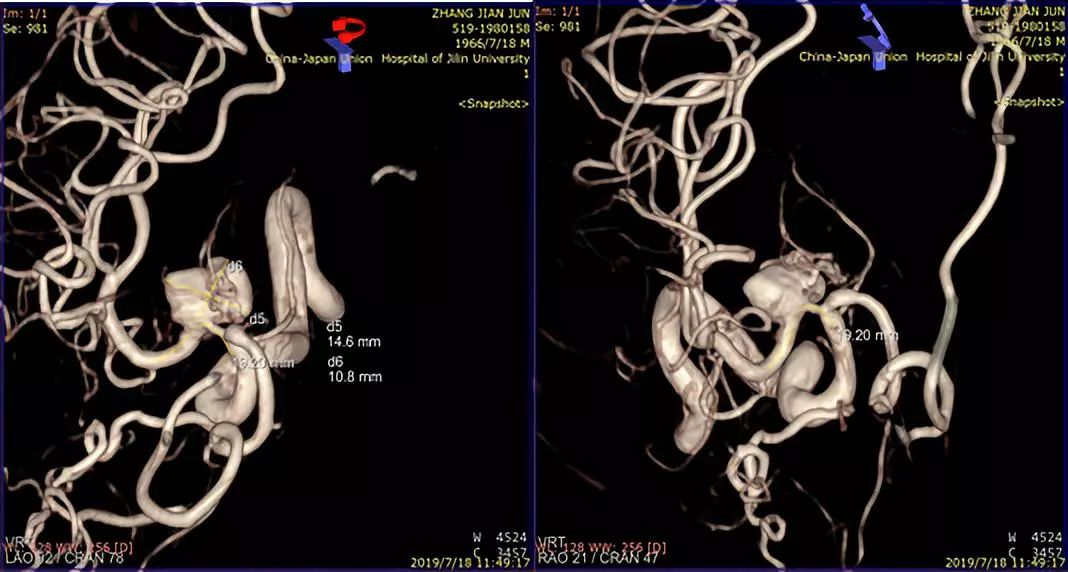

术前造影:

此患者为一53岁的男性患者,因发现右侧大脑中动脉M1段动脉瘤2周而住院治疗。从患者影像学资料分析,患者动脉瘤的形态学很不稳定,而且有明显增大的趋势,血流滞留很明显,斟酌夹层动脉瘤可能性较大。患者有头痛的病史,对比两周前的影像资料,动脉瘤有增大趋势。患者治疗意愿比较强烈。造影结果显示,患者夹层动脉瘤上方有一较大的分支动脉—豆纹动脉。请神经外科会诊,会诊意见:手术干预难以保存豆纹动脉,开颅手术不具有治疗优势。与患者及患者家属沟通后,患者及患者家属积极要求介入治疗。

术前讨论:如何使患者获得最大受益?因为是夹层动脉瘤,如果填圈治疗,一是外侧豆纹动脉会即刻闭塞,更易引起临床症状;二是填圈治疗有使夹层动脉瘤撕开、出血的风险。所以经讨论我们决定采取一种折中方案,只放密网支架而不填圈的手术方式。我们希望通过密网支架的支撑,使夹层动脉瘤慢慢消失。通过慢性闭塞,给夹层动脉瘤上方的豆纹动脉部位一个代偿血管增生的时间,减少患者发生偏瘫的概率。经过精准测量后,选择合适支架。术中手术顺利,术后进行血管三维重建,密网支架放置良好,贴壁良好,能够清晰的看到豆纹动脉。术后患者回到病房后,一般情况良好。术后18小时后患者出现言语含糊、左侧中枢性面舌瘫,左侧肢体偏瘫,CT排查出血后斟酌是患者夹层动脉瘤上方的豆纹动脉闭塞引起的症状。立即行全脑血管造影,发现豆纹动脉确实消失。确定豆纹动脉消失是引起患者临床症状的一个主要原因。这是天坛医院第一例在密网支架植入术后第一天就复查造影的患者。造影结果让我们惊喜的发现,密网支架治疗后,不到18个小时,患者的动脉瘤几乎完全消失。从而证明,我们的手术通过精准测量,选择合适的密网支架对夹层动脉瘤的治疗效果以及夹层的修复效果是非常明显的。当然,患者出现穿支动脉的闭塞,是我们术前充分斟酌的,且无法避免的一个并发症。术后给予神经康复,高压氧治疗,患者有明显的好转趋势。我们希望通过后续的康复治疗能够使患者的生活接近正常,同时我们也在密切随访患者,希望患者动脉瘤完全消失,并且正常生活。